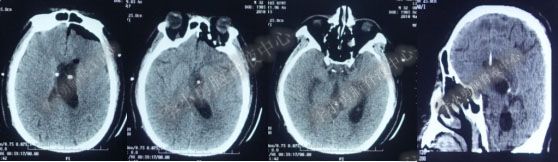

入院第13天即2018年6月6日出现恶心、呕吐,复查头部CT(图-23)显示幕上脑室略有扩张,四脑室明显变大。

图-23:2018年6月6日术前头部CT

图-24:2016年6月6日术后头部CT

入院第16天即2018年6月9日患者意识变差,复查头部CT(图-25)发现双侧脑室扩大,尤其以左侧为重,脑室有大量气体,可能与术后病人烦躁和伤口缝合不严密相关。

图-25:2018年6月9日头部CT

入院第19天即2018年6月12日,病情控制平稳,按计划行侧脑室腹壁外引流术前例行性的头CT检查示脑室内气体部分吸但脑室有所缩小(图-26)。

图-26:2018年6月12日头部CT

图-27:2018年6月12日术后头部CT

入院第27天即2018年6月19日左侧脑室额角外引流管关闭3天,患者意识清楚,四肢活动良好,同侧枕角外引流管通畅,在病房拔除额角引流管。术后当天复查头部CT示拔管后颅内无出血,脑室引流完好,脑室内还剩3根管(图-28)。

图-28:2018年6月19日头部CT

图-29:2018年6月23日术后复查头CT

入院后35天即2018年6月27日,病情明显好转:意识变清楚,四肢自主活动正常,体温连续2周余正常(图-30)。

图-30:2018年6月27日头部CT

图-31:2018年7月11日头部CT

因四脑室外引流管共3周未引流出脑脊液,且期间多次脑CT显示四脑室再无扩张,因此在入院第53天即2018年7月12日行四脑室引流管拔除术。术后当天复查头部CT脑室系统引流正常,四脑室引流管拔除,仅剩1根(图-32)

图-32:2018年7月12日头部CT

入院第89天即2018年8月20日例行性复查头部CT显示脑室系统引流良好(图-33)。

图-33:2018年8月20日头部CT